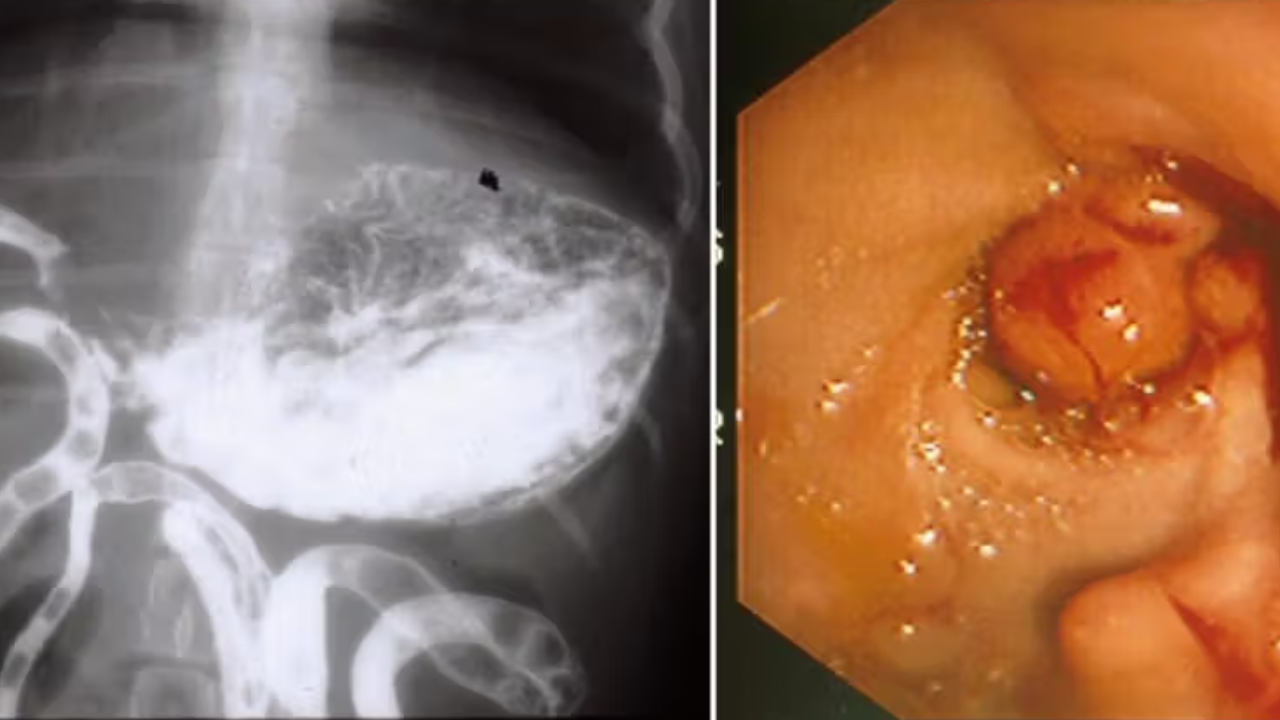

Accurate Diagnosis: By employing procedures which include manometry, endoscopy, or imaging studies to identify the problem.

Endoscopic Interventions: Conservative measures in the management of patients with esophageal and gastric motility disorders.